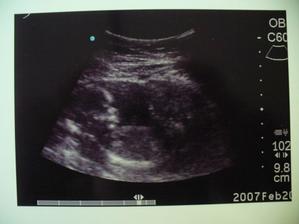

SRPŇÁTKA 2007 - fotky UTZ

album věnované mimískům, které se narodí v srpnu 2007 a jejich maminkám ze "Společného termínu SRPEN"